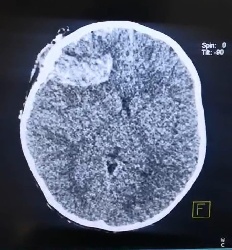

تعرضت طفلة تبلغ من العمر سنتين إلى إصابة بالغة في الرأس بعد سقوط مروحة سقفية عليها ، مما أدى إلى تمزق في فروة الرأس و تهشّم في جمجمتها ، وتهتك خطير بغشاء السحايا و خروج أجزاء من الدماغ. و أكد مسؤول إعلام المدينة الطبية علي الجابري ان (الطفلة (ح.ع) تم نقلها إلى جراحة مدينة الصدر الطبية ، حيث خضعت لسلسلة من الفحوصات الطبية و الأشعاعية ، و التي أكدت خطورة الإصابة .

و بين العكايشي ان (العملية الجراحية استغرقت ساعتين ، حيث تمكن الفريق الطبي من إيقاف النزيف و إصلاح التمزقات في الدماغ و غشاء السحايــــــا ، وإستئصال الأجزاء التالفة من الجمجمة). مضيفاً ان العملية نجحت والطفلة نجت دون حدوث مضاعفات خطيرة تذكر). و أشار الى تماثل الطفلة للشفاء و التي ترقد حاليًا في ردهات الجملة العصبية في مدينة الصدر الطبية .